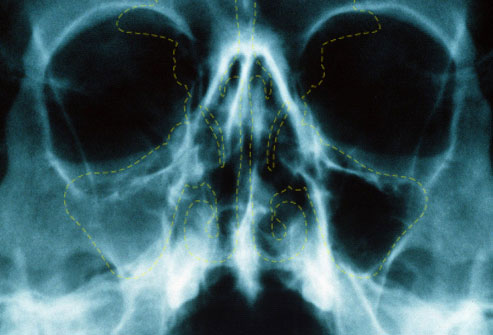

нормальные гайморовы пазухи носа

Рис. 3. Гайморові пазухи носа в нормі.

Рис. 4. На рентгенограмі бачимо тотальне затемнення правої гайморової пазухи в результаті запального процесу.

Рентгенологічне дослідження дозволить виявити всі щільні структури всередині гайморової пазухи: секрет, ущільнену слизову оболонку, потовщену або зруйновану кісткову стінку , поліпи, кісти і новоутворення.

Чіткий контур стінок пазухи і рівномірне зниження прозорості говорить про гострий синусит. Якщо разом зі зниженням прозорості гайморової пазухи відзначається ущільнення її бічної стінки, то говорять про хронічному гаймориті. Якщо в результаті хронічного гаймориту утворився свищ, то виявлення кісткового дефекту в стінці пазухи діагностується за допомогою введення в свищевой хід зонда.

справа норма, слева – левосторонний гайморит

Рис. 7. Справа на рентгенограмі вид гайморових пазух в нормі. Зліва — лівобічний гайморит.